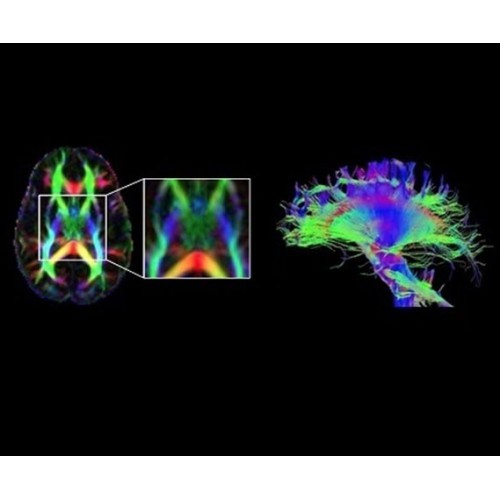

В систему SIGNA PET/MR встроены запатентованные детекторы кремниевого фотоумножителя (SiPM) и сверхчувствительные кристаллические сцинтилляторы на основе лютеция толщиной 25 мм. Благодаря этому обеспечивается исключительная чувствительность и возможность использования времяпролетной диагностики (TOF).

Кроме того, в результате использования технологии TOF и инновационной технологии реконструкции Q.Clear вы сможете добиться прекрасного соотношения сигнал/шум. А благодаря технологии нулевого времени эхо (ZTE) визуализировать костную структуру без ионизирующего излучения. Все эти разработки для улучшения качества сканирования и точности анализа помогут вам использовать весь потенциал ПЭТ/МРТ.

• Специальный пакет приложений для измерения и сравнения объемных изображений ЦНС с нормами поможет вам в диагностике нейродегенеративных заболеваний, а дополнительные инструменты визуализации — в постановке точного диагноза с помощью бета-амилоидов и радиоизотопных маркеров ФДГ.